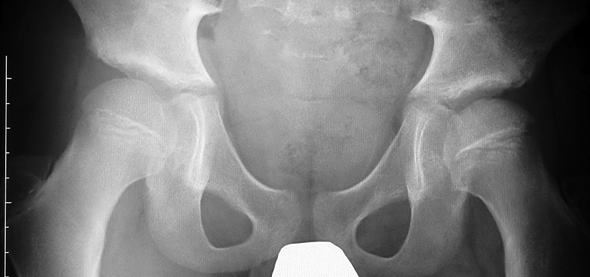

10歳男子の右ペルテス病。この年齢になると骨頭そのものが大きくなってくる。その為、内反骨切りだけで骨頭を臼蓋の中に入れようとすると内反角度が大きくなり、結果的に脚長差が著しくなってしまう。あらかじめ骨盤骨切りを行い、ある程度臼蓋で骨頭を覆っておくと、内反角度を小さく抑えることができる。